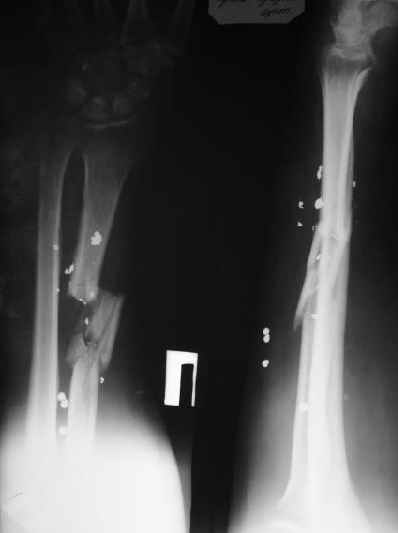

Alexander Chelnokov 16 Март 2004, 18:00

1

Пока мы наложили аппарат для восстановления оси и длины лучевой кости. Снимок прлагаю.